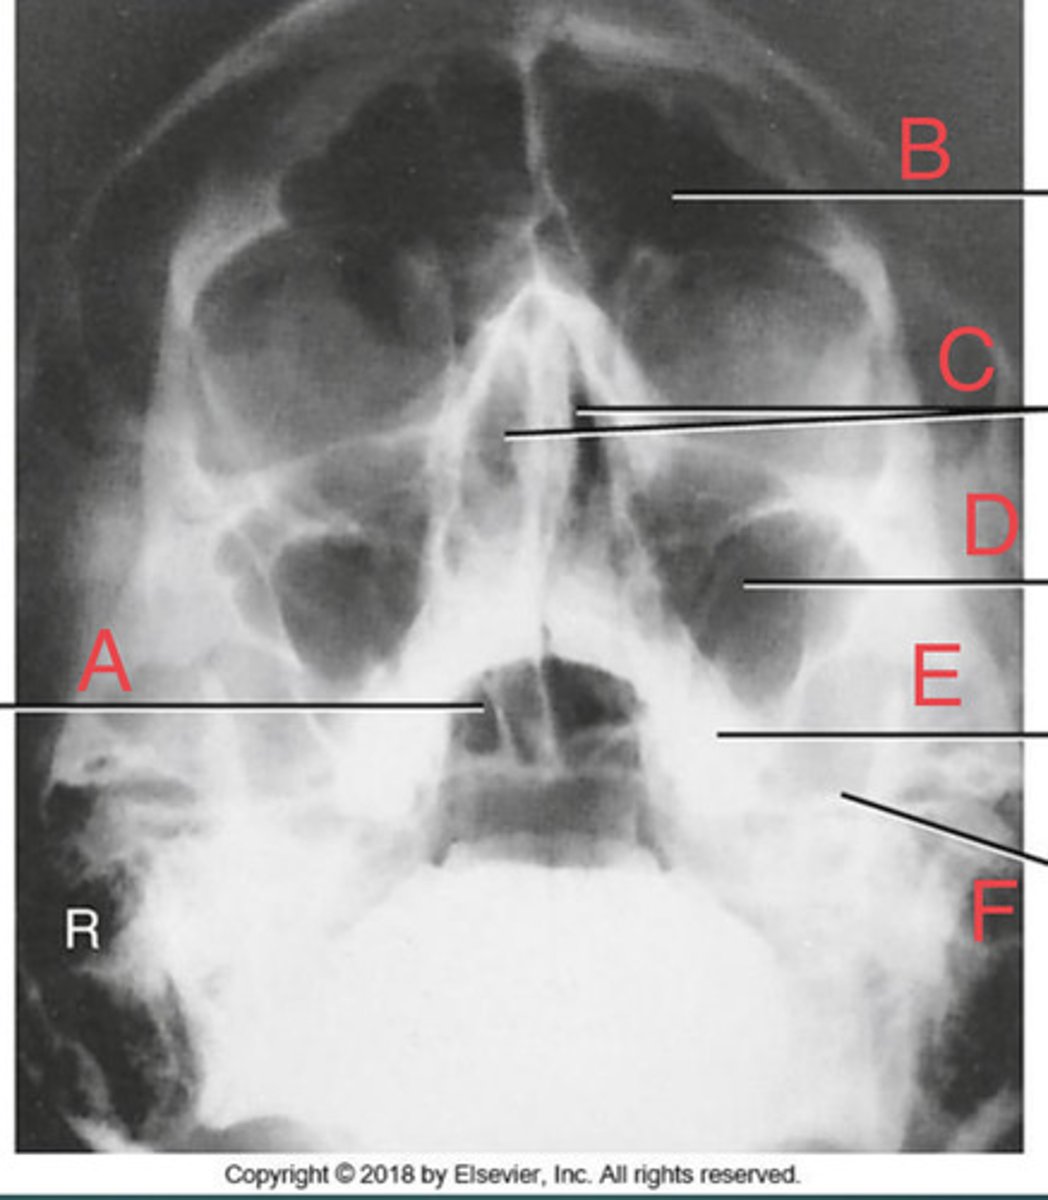

Waters sinus method

What projection?

r. frontal sinus of the frontal bone

A.

R. Maxillary sinus of maxilla

B.

R. petrous ridge of temporal bone

C.

bony nasal septum

D.

L. inferior orbital fissure of sphenoid bone

E.

Sphenoid sinus of sphenoid bone

F.

bony nasal septum

E.